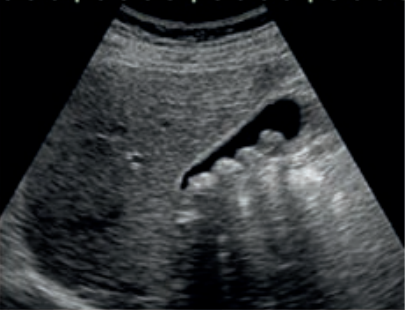

Jakie struktury anatomiczne uwidoczniono na obrazie USG?

Ilustracja do pytania 33

A. Pęcherz moczowy z kamieniami.

B. Ciężarna macica z czterema płodami.

C. Nerka lewa ze złogami.

D. Pęcherzyk żółciowy z kamieniami.